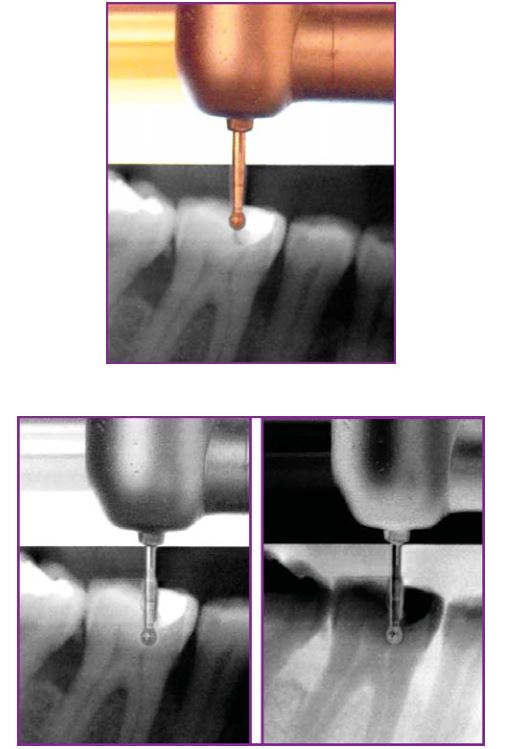

Có thể xác định độ sâu trần tủy bằng cách đặt mũi khoan lên phim để ước lượng (H5.3).

Khi đã có cảm giác hẫng tay thì chứng tỏ phần trần tủy đã thủng, nên sử dụng các mũi khoan có đầu tận cùng an toàn để tiếp tục (H5.4).